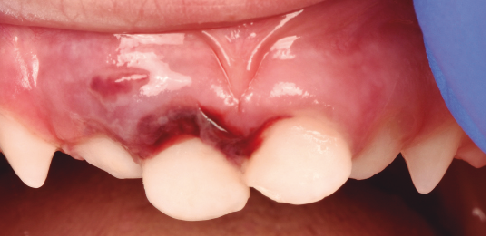

Fotografía clínica inicial, 15 horas después del traumatismo. Fotografía clínica inicial, 15 horas después del traumatismo.

Tratamiento de dos fracturas radiculares y luxación lateral en una paciente de 3 años

Los traumatismos dentoalveolares representan un 5% de los traumatismos corporales, y ocurren tanto en pacientes adultos como en niños. Un 25% de los niños en edad escolar sufrirá un traumatismo dental en su dentición temporal o permanente. Las fracturas coronales son las más frecuentes en la dentición permanente, mientras que, en la dentición temporal, son las luxaciones. Realizar un correcto diagnóstico, tratamiento de urgencia y seguimiento a lo largo del tiempo es fundamental para prevenir complicaciones en el futuro. El objetivo de este artículo es presentar el diagnóstico, tratamiento de emergencia y seguimiento de un caso clínico de traumatología dental en una paciente de 3 años de edad.